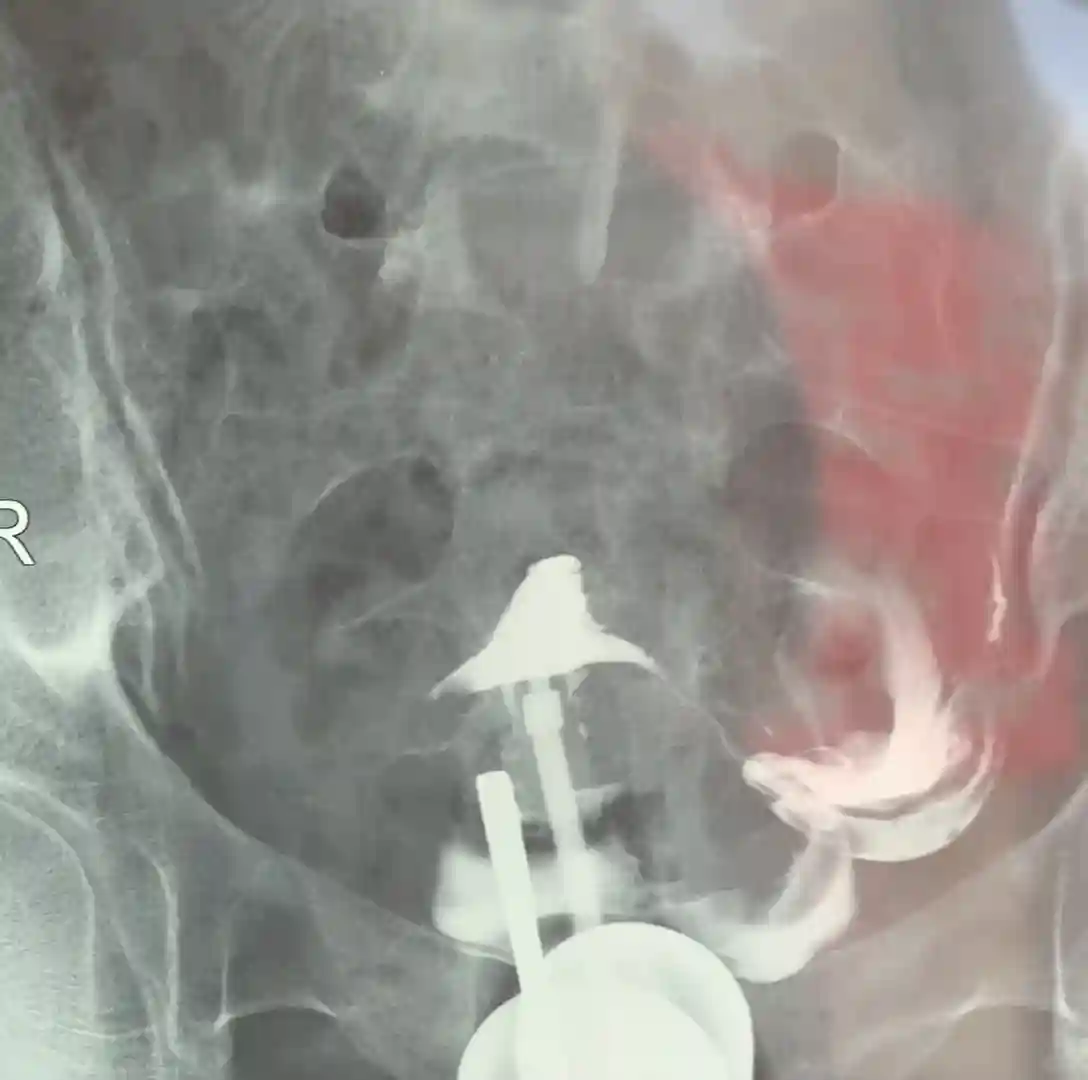

决定去北京妇产医院做造影

直接去北京妇产医院找苗杰主任做造影

我右侧宫外峡部妊娠,开窗取胚,

是输卵管最细的部位

1月13日做造影,痛感可以忍受

造影结果左侧通畅,右侧堵塞了,